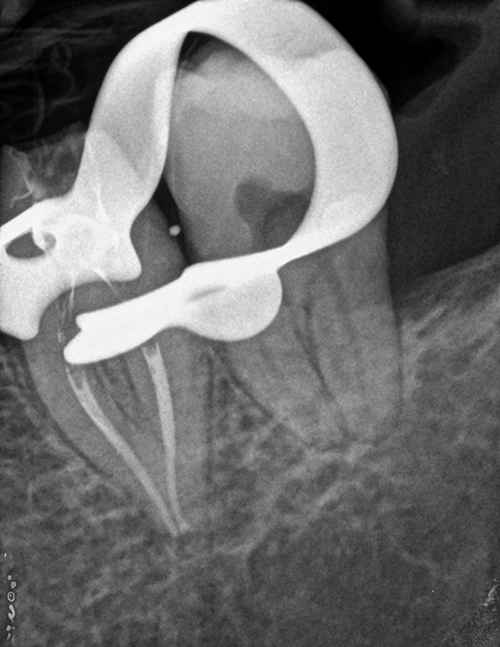

Post trattamento

Il trattamento endodontico consiste nella rimozione della polpa infiammata ed infetta, e nella sua sostituzione con un’otturazione permanente in guttaperca e cemento canalare, previa adeguata detersione e sagomatura dei canali radicolari con strumenti manuali e rotanti.

In caso di un trattamento endodontico primario incongruo o fallito, bisogna intervenire nuovamente con un ritrattamento in cui si ripuliranno in maniera adeguata i canali radicolari per tutta la loro lunghezza e tridimensionalità. Nel caso fosse presente un granuloma, il ritrattamento dovrà portare ad una guarigione della sintomatologia e alla scomparsa radiografica della lesione nell’arco di circa 6-12 mesi, ma spesso è necessario anche più tempo.